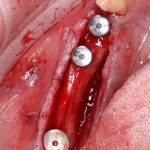

Рекомендации по установке имплантов. Для всех. Часть V.